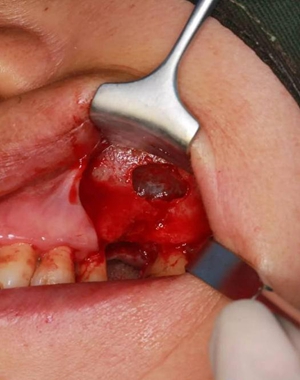

改良式外提升工具盒-外提 科貿(mào)嘉友收錄

六個(gè)月之后